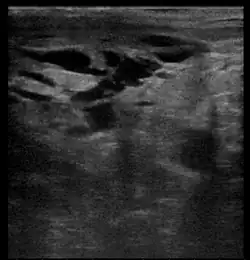

Breast ultrasound is the use of medical ultrasonography to perform imaging of the breast. It can be used as either a diagnostic or a screening procedure.[38] It may be used either with or without a mammogram.[39]

Diagnostic anatomic ultrasound looks at the anatomy whereas diagnostic functional ultrasound records information such as blood flow or tissue characteristics. A specific functional form of ultrasound is elastography which measures and displays the relative elasticity of tissues, which can be used to differentiate tumors from healthy tissue.[40] Recent studies have shown that shear wave elastography in primary invasive breast carcinoma could be useful for indicating axillary lymphadenopathy.[41]

Ultrasound is also used surgically. Specifically, an ultrasound-guided needle biopsy allows providers to see the needle so it can be directed toward the lesion of concern while avoiding other critical structures such as blood vessels.[40] Ultrasound-guided biopsies have also been shown to decrease re-excision and mastectomy rates in breast cancer. A recent study found 100% ultrasound localization with negative margins obtained in both non-palpable and palpable lesions at initial procedure. In line with this, intraoperative ultrasound guided breast conserving surgery is being increasingly used by breast surgeons worldwide[42]

Contrast-enhanced ultrasound (CEUS) imaging has also been researched and shows similar sensitivity to MRI in detecting breast cancer across lesions of similar size. Additionally, the combined use of MRI and CEUS in lesions > 20 mm has been shown to optimize the diagnostic specificity and accuracy in breast cancer prediction.[43]